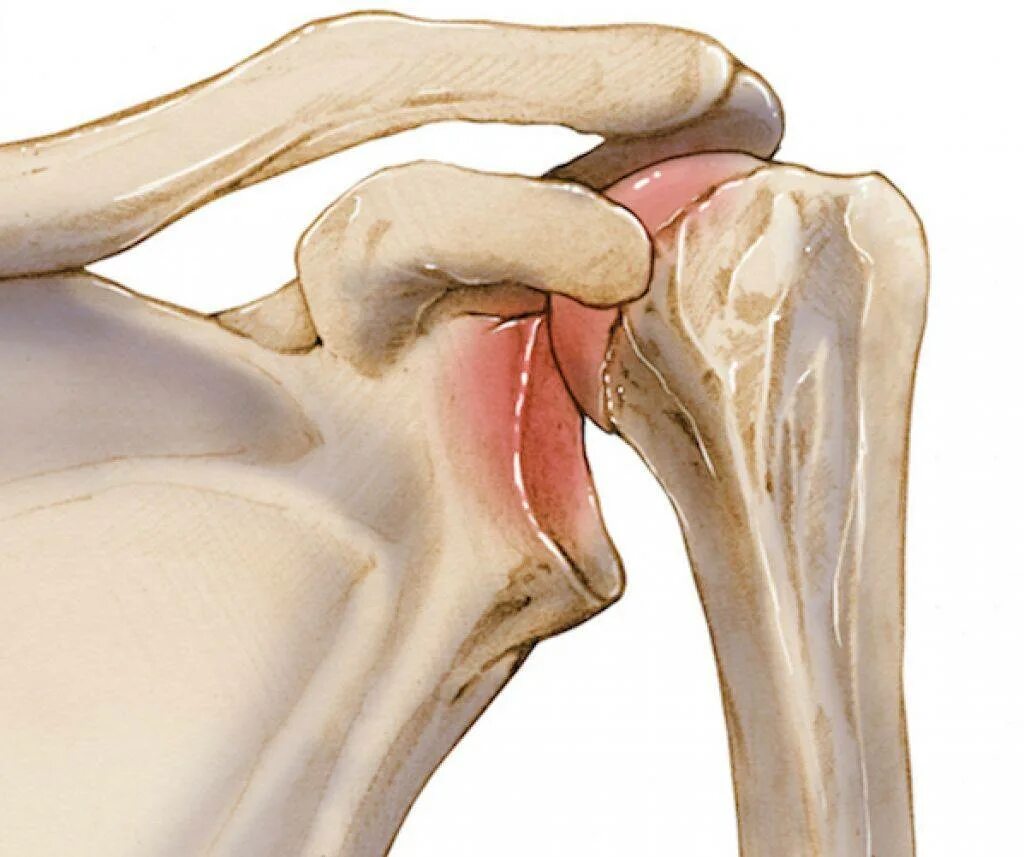

Вывих плеча вверх